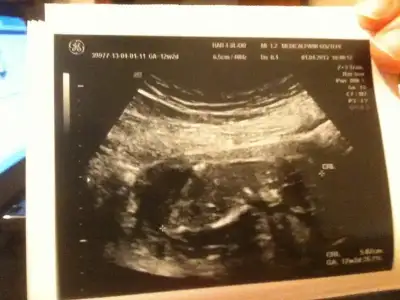

dr soylemeden siz gorun genital nub teorisi ( bebegin cinsiyeti)

anlayan arkadaşlar sizce nub belli mi cinsiyet konusunda bir fikriniz var mı?

11.haftada dr. cinsiyetine önce kız dedi, sonra pipi gördüm dedi, sonra da kordon olabilir dedi, yani bilemedi, orkidem kız demişti. 16.haftada başka bir dr. %98 kız dedi.

18.haftada kendi doktorum erkek dedi ve pipiyi gösterdi.

lakin biz emin olamadık, kafamız karıştı.

21.haftada ayrıntılı ultrason için gittiğimiz perinatoloji uzmanı (prof.) erkek dedi, biz de gördük pipiyi.